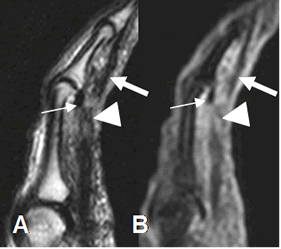

Fig 69. Lesión del mecanismo flexor.

A: RM sagital en T2 y B: RM sagital en STIR. Ruptura de los tendones flexores sobre la falange medial del 5º dedo. (Punta de flecha). Tendón superficial (Flecha delgada) y profundo (Flecha gruesa). Adicionalmente hay ruptura del mecanismo de poleas.